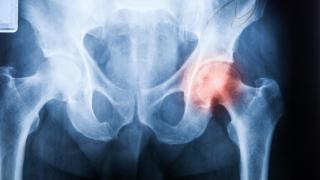

Imagen de archivo de un médico examinando una radiografía de una cadera.

Imagen de archivo de un médico examinando una radiografía de una cadera. iStock